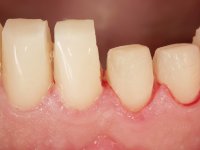

Realizado o diagnóstico e tomada a decisão quanto ao tratamento a executar, tornou-se importante definir qual a sequência de trabalho a adotar no sentido de conseguir a reabilitação da D.V.O. (V.D.O), de forma progressiva e equilibrada. Na primeira fase fez-se uma pré-impressão da arcada inferior com silicone tipo “putty” e em seguida realizou-se o preparo dentário de todo o sector posterior. O preparo para os overlays foi feito coronalmente à linha amelo cementaria no sentido de ser o mais conservador possível. A impressão foi feita com técnica de dupla mistura após afastamento gengival realizado com pasta de caulino. A provisória foi realizada com resina composta de polimerização dual. Em laboratório foram realizados os overlays após se ter aberto ligeiramente (1,5mm) a D.V.O. nos modelos montados em articulador semi-ajustável. Simultaneamente o sector antero-inferior foi encerado no sentido de acompanhar este aumento da D.V.O. Também foi confecionada uma chave de silicone translucido para posterior confeção dos provisórios antero-inferiores. Em boca foi primeiro realizada a provisionalização dos dentes anteriores utilizando resina composta previamente aquecida após preparação das superfícies dentárias para a adesão. Foi colocado o dique de borracha para promover o isolamento absoluto e posteriormente foram colados os overlays. Em laboratório foi realizada nova chave de silicone para confecionar os provisórios antero-superiores. Seguidamente em boca foram preparados os seis dentes antero-superiores após colocação do fio de afastamento gengival. Feita a preparação adequada das superfícies dentárias foi realizada a impressão com técnica de dupla mistura e a respetiva provisória. Em laboratório foram confecionadas 6 facetas feldespáticas num modelo de trabalho tipo “Geller”. A provisória foi removida e as facetas foram coladas em boca utilizando um isolamento relativo competente. Esta opção foi tomada em virtude de uma prévia experiencia negativa com a colocação do dique de borracha na mandibula. Após a colagem dos laminados antero-superiores foram dadas 12 semanas para avaliar a adaptação do paciente à nova situação e então iniciar a confeção das facetas antero-inferiores. Após colocação do fio de afastamento gengival. foram feitos os preparos dentários adequados e em seguida foi feita a impressão. Também foi feita a preparação do dente 3.4 que, entretanto, tinha sofrido uma fratura do overlay. As facetas e a restauração do 3.4 foram realizadas num modelo de trabalho tipo “Geller”. Após remoção da provisória, as facetas foram coladas em boca, utilizando um isolamento relativo pelas razões apontadas anteriormente. Após colocação do trabalho o paciente foi reabilitado por outros colegas com um implante na zona do 2.6 e substituição da coroa aparafusada sobre o implante colocado no local do 3.5. Posteriormente surgiram fraturas nos overlays dos dentes 4.7 e 3.7 que foram reabilitados com overlays em Zr.